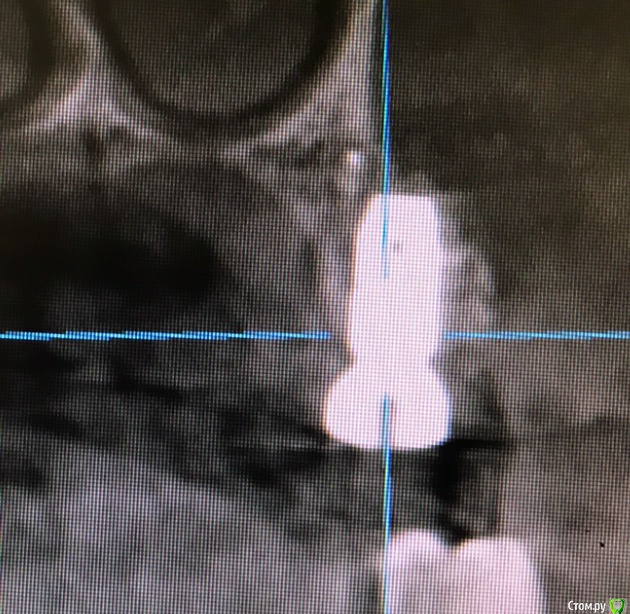

колесников Опубликовано 15 марта, 2019 Автор Поделиться Опубликовано 15 марта, 2019 Вот так выглядит интегрированый графт и соответственно не созревший. Время ожидания примерно равнозначное Ссылка на комментарий

колесников Опубликовано 16 марта, 2019 Автор Поделиться Опубликовано 16 марта, 2019 (изменено) Ну как бы тут все очевидно. Слева стала костью,справа нет. Но должен вам отметить,что даже в случае неудачи (как кажется)потери нет. Задача стояла не увеличить объём для имплантации или укрыть Имплант,а снять напряжение с вершины гребня и дать созреть десне. Имплант в нативной кости,он интегрирован,десна успела созреть за это время,возможно будет не так объёмно как хотелось бы,но у меня в запасе этап раскрытия ,фдм зарос ,есть с чем поработать. Все что не интегрировалось ,лизируется самостоятельно,выскребать ничего не нужно,ещё подождать. Изменено 16 марта, 2019 пользователем колесников Ссылка на комментарий